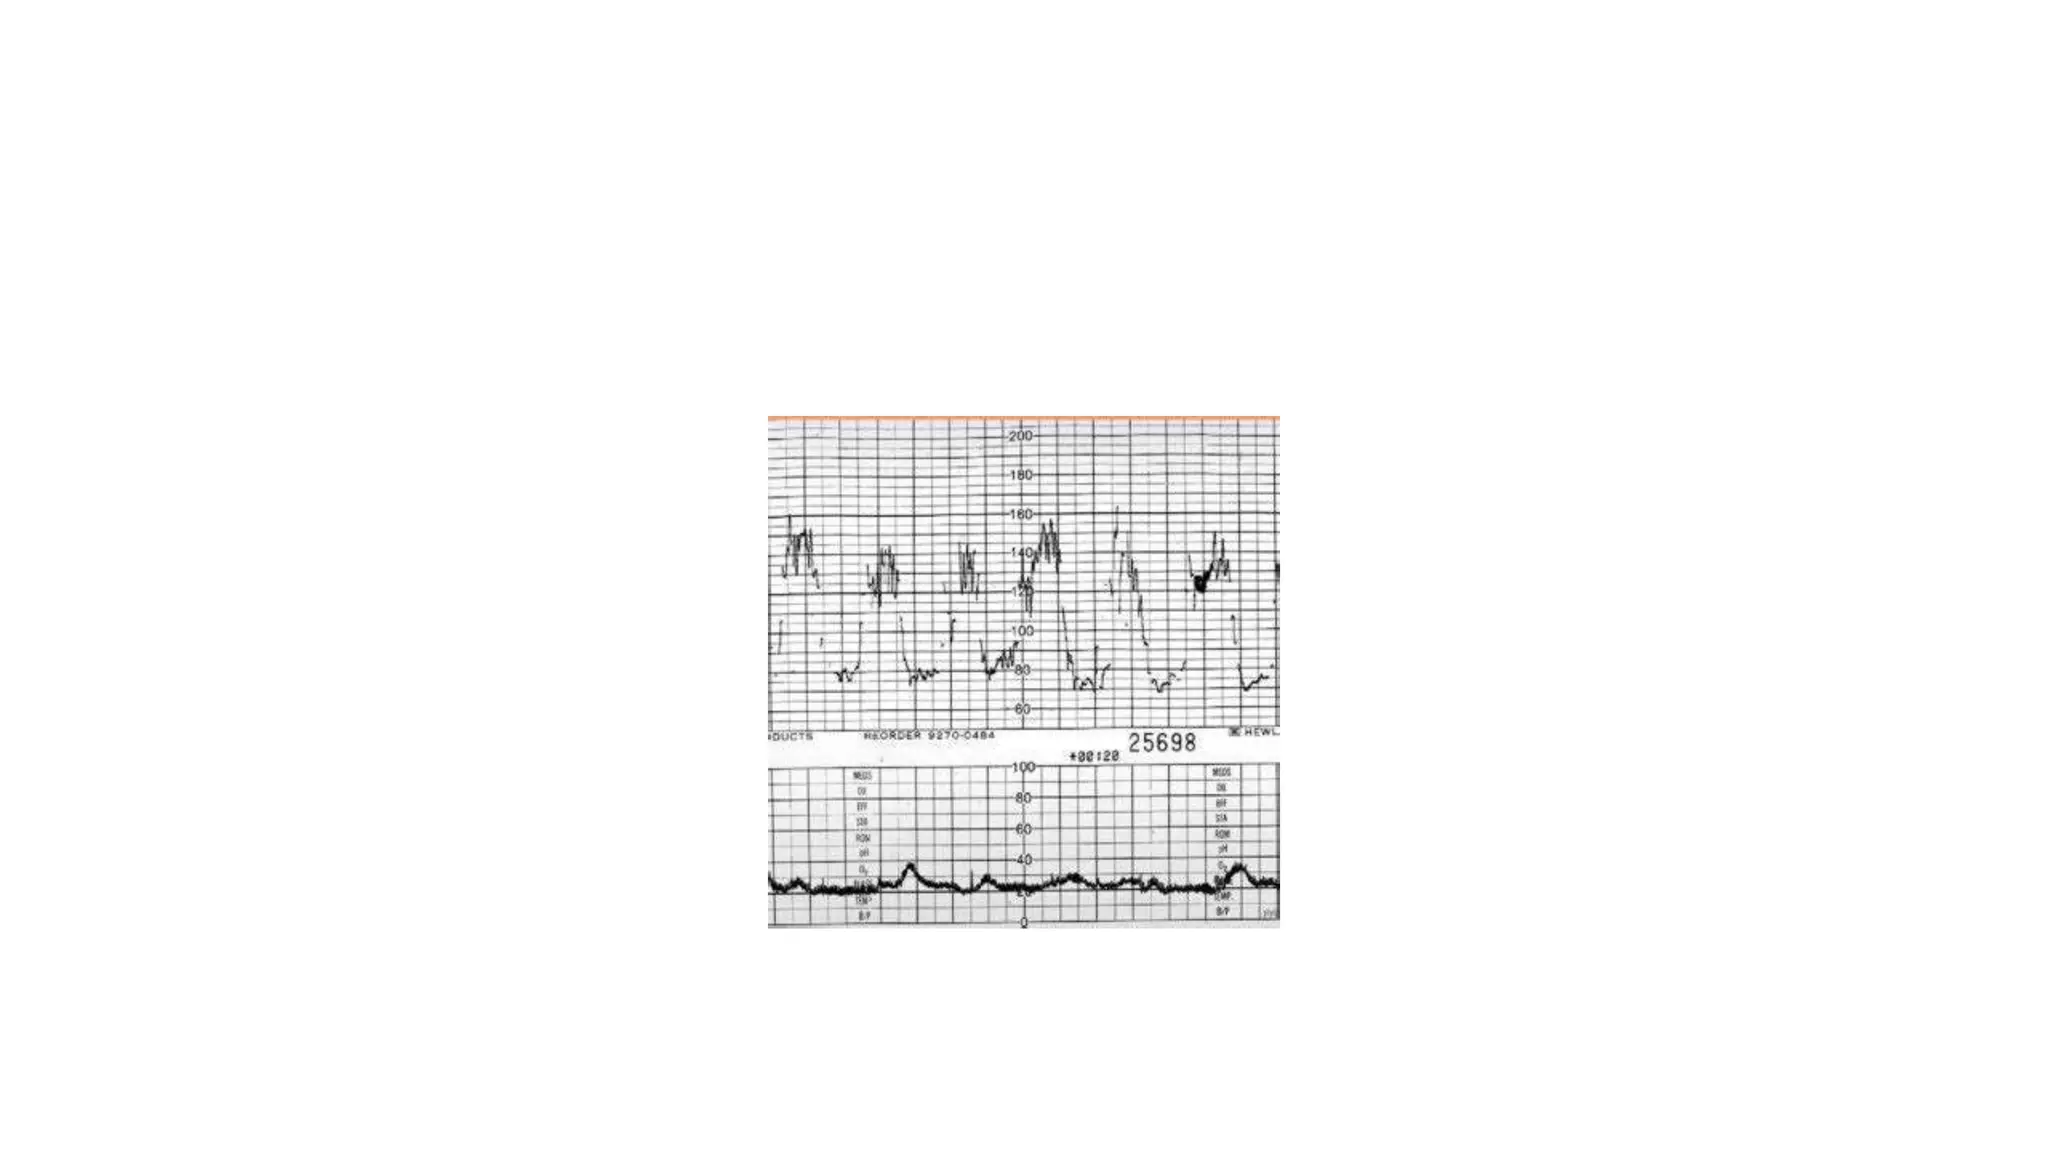

The document discusses key metrics for monitoring a baby's heart rate in utero, including the normal baseline rate of 100-160 bpm and variability. It also covers types of accelerations and decelerations that can occur, such as early or late, as well as bradycardia, which is an abnormally slow heart rate.